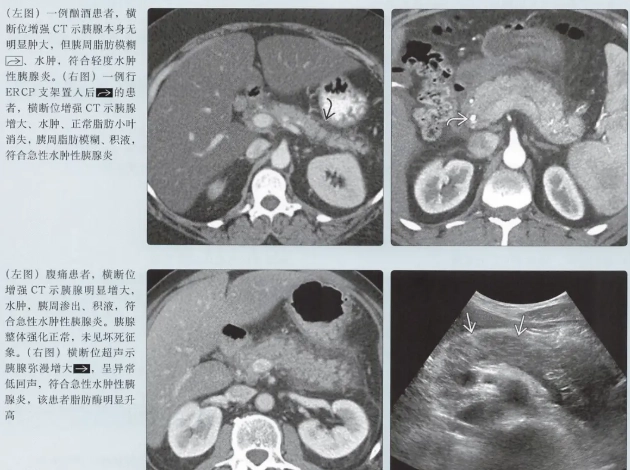

一個常見的認知誤區:很多人以為腹痛減輕就代表好轉。在壞死性胰臟炎的病程中,有時腹痛感會因為神經末梢也壞死而暫時減輕,這反而是病情惡化的危險訊號,絕非好轉跡象。必須結合血液檢查(如C反應蛋白CRP)和影像學(電腦斷層)來判斷。